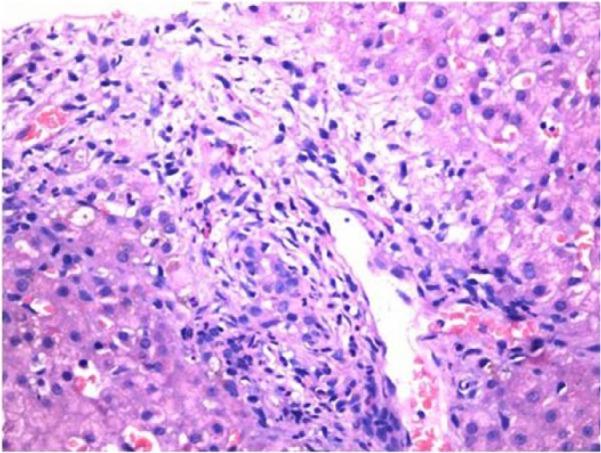

Cholestasis can occur in newborns due to infections. However, the manifestations of the underlying infections usually dominate the presentation. We present a 2-month-old infant who presented with jaundice and no fever or signs of systemic illness. Liver biopsy was suggestive of cholangitis. He was subsequently detected to have urinary tract infection with . The child was treated with appropriate antibiotics for 2 weeks following which the cholestasis resolved. Thus, neonatal cholestasis due to infections can also occur in the post-neonatal period without clinical manifestations of an underlying infection.